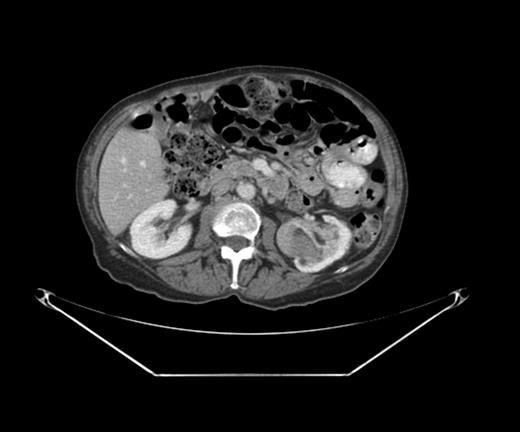

A PET-CT was performed, which demonstrated a round enhancing 1.8 × 1.5 cm right subpectoral lymph node with FDG uptake and a maximum SUV of 4.0 suspicious for metastatic disease (Figs 1 and 2). Additionally, an incidental 4.1 × 3.4 cm mass within the midpole of the left kidney was heterogeneously enhancing with increased FDG uptake and a maximum SUV of 8.6 suspicious for a renal cell carcinoma or less likely a transitional cell carcinoma (Figs 3 and 4).